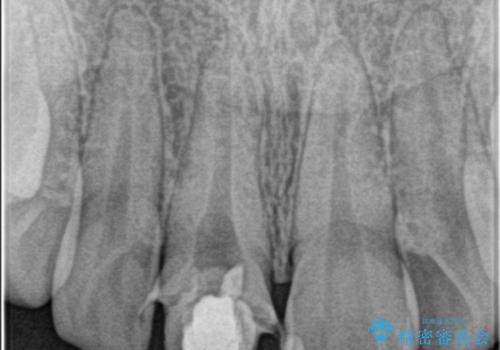

- 前歯が欠けたとの事で来院。

セラミックを希望されたので根管治療からやり直しました。

- ジルコニアクラウンスタンダード・仮歯 13.2万円 精密根管治療(リトリート)・ファイバーコア 12.1万円費用は治療当時の料金となります